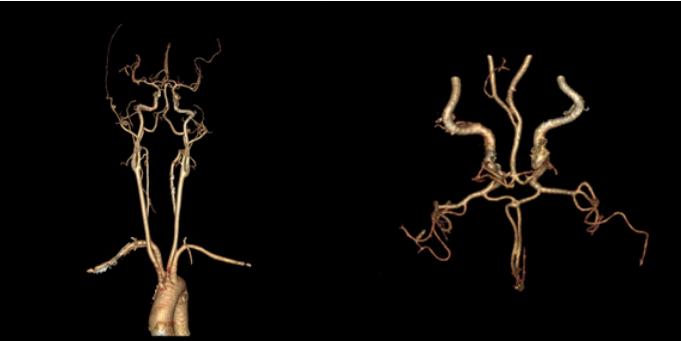

八、混合型脑动脉开窗畸形

病例15::左侧大脑前动脉A1、基底动脉起始段开窗畸形

病例16:基底动脉近段、右侧椎动脉开窗畸形